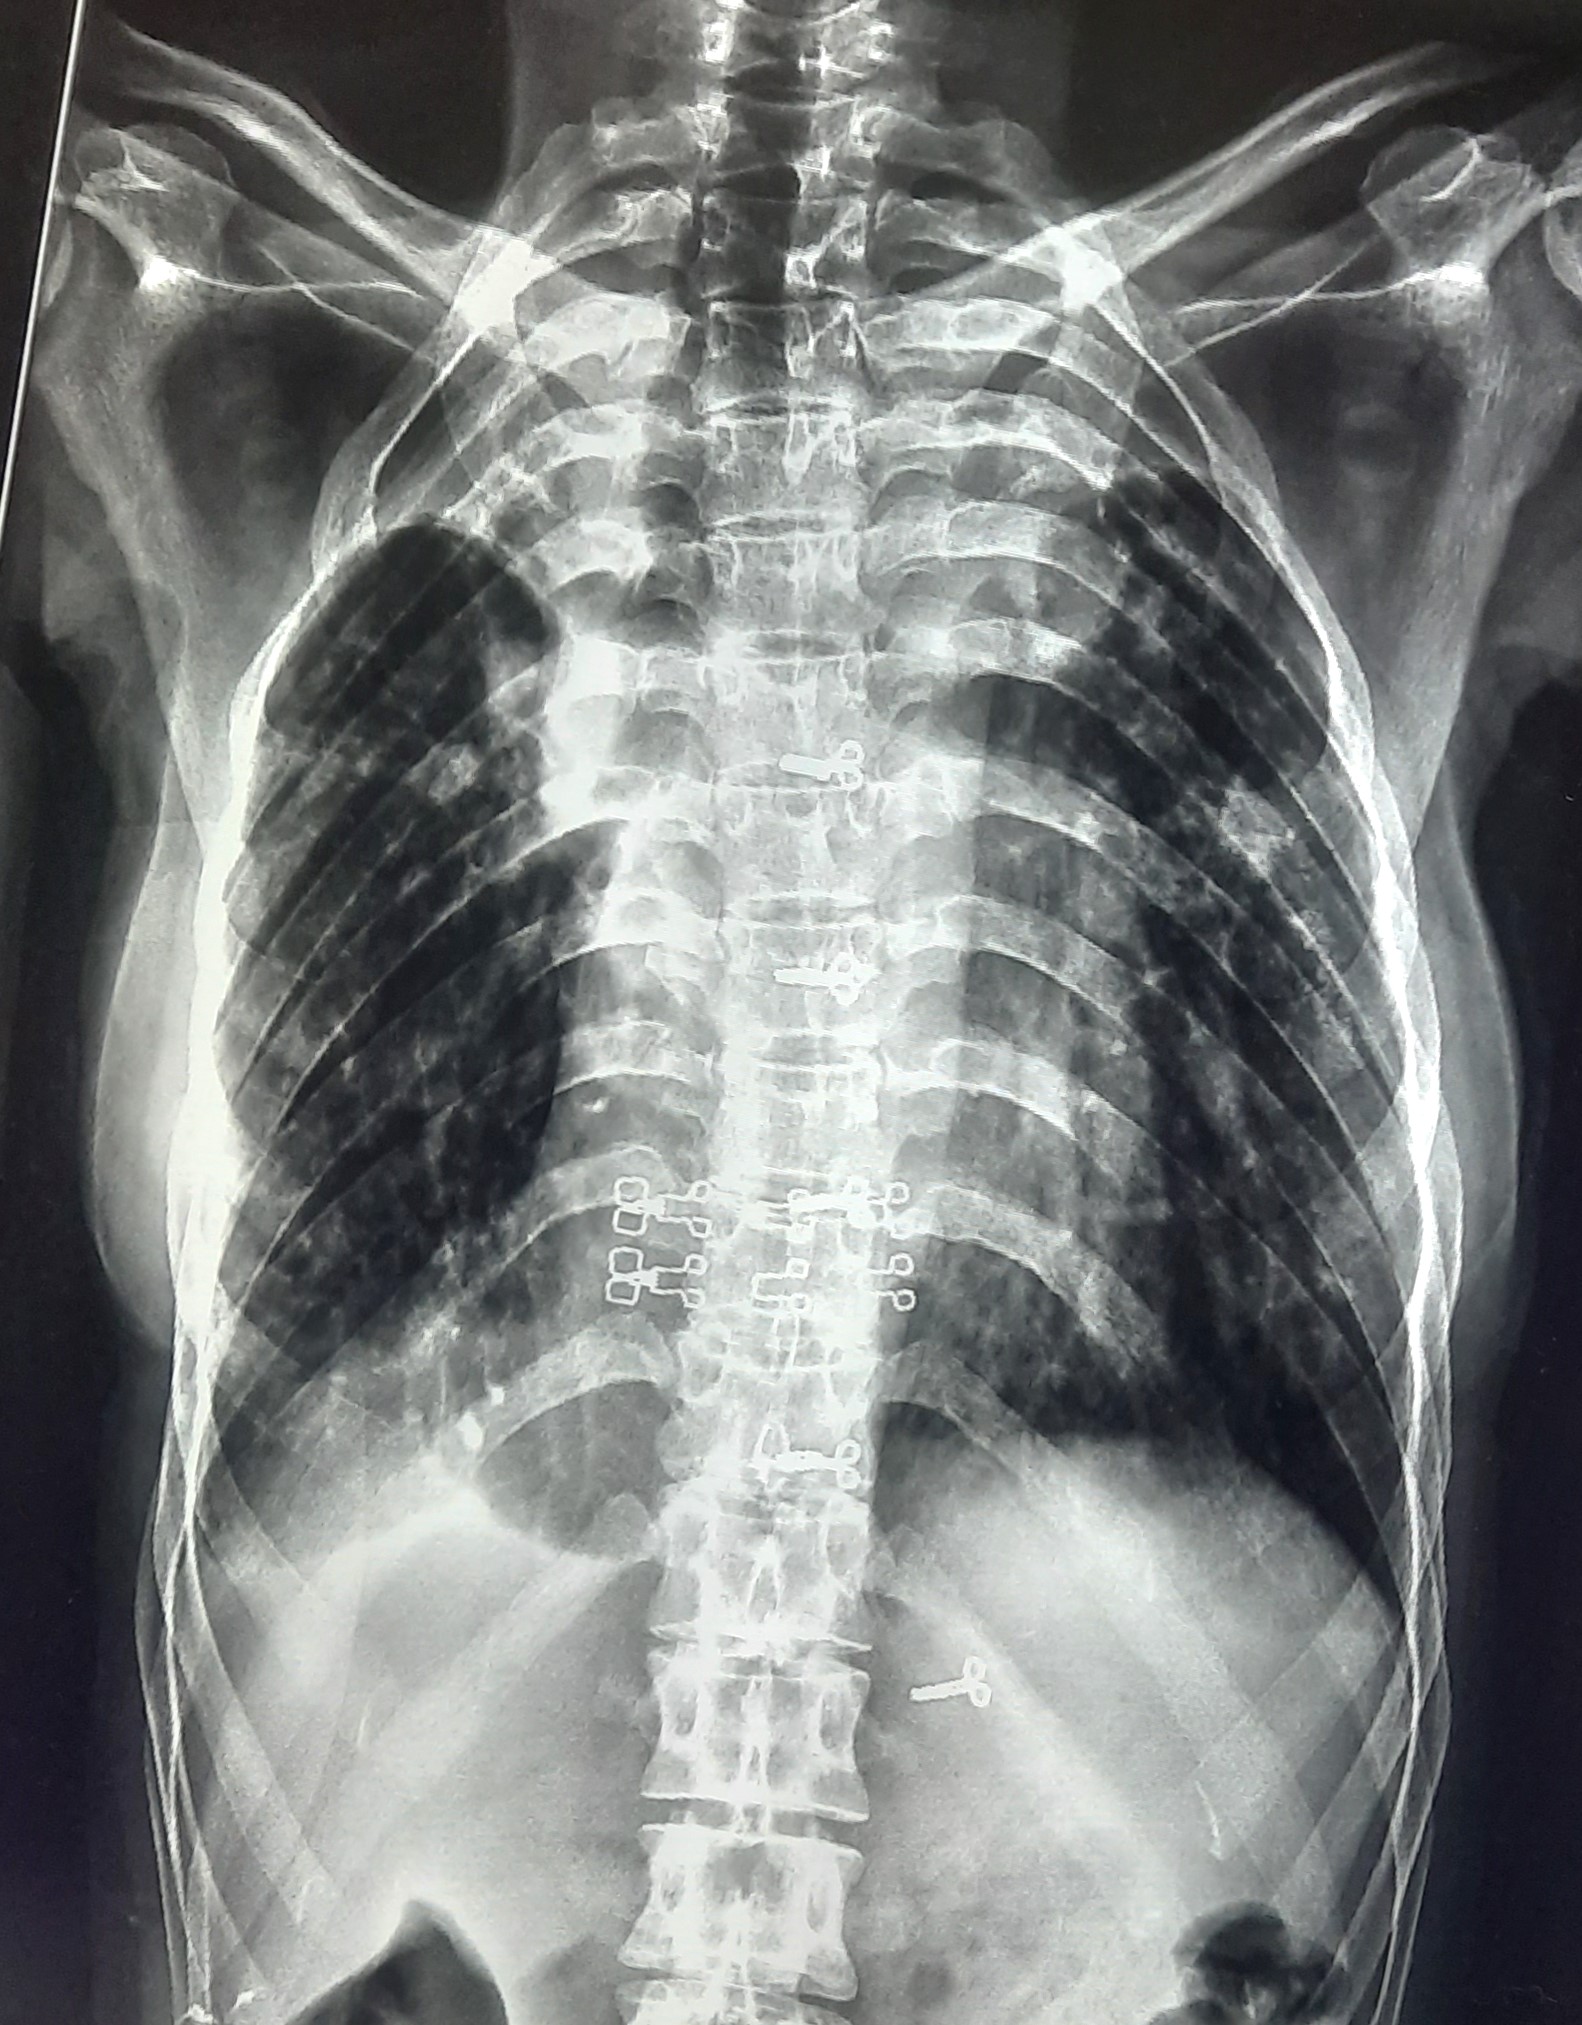

| 51 | IGGMC, Nagpur, Nagpur | P2 | 29-4421 | Santosh Neware | Consent taken on Paper | 40 Yrs. |

Provisional Diag : Pulmonary Tuberculosis

Final Diag : Pulmonary tuberculosis (Microbiologically Confirmed PTB) |

TB Case (Confirmed) | Right Upper & mid zone fibro cavitary lesion present, upward pull of right hemidiaphragm, tracheal pull right sided | Abnormality visible on x-ray |